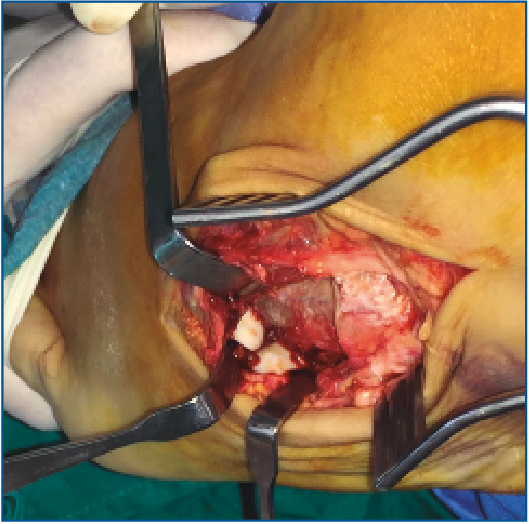

Es intervenido a la semana de la lesión realizándose, bajo anestesia raquídea e isquemia del miembro, una incisión dorsolateral desde la articulación calcaneocuboidea hasta la base del 4.º MTT. Se expuso el cuboides reflejando el extensor corto a dorsal y peroneo corto a plantar y se evidenció la desalineación del cuboides con el 4.º y 5.º MTT y el calcáneo creada por la luxación. Se realizó una reducción manual del mismo y una fijación con 2 agujas de Kirschner (agujas K) metatarsocuboideas, 1 aguja cuboideocalcánea y 1 calcaneocuboidea, realizándose al mismo tiempo una fijación de la apófisis lateral del astrágalo con un tornillo canulado (Figuras 3, 4 y 5). Se mantuvo 6 semanas inmovilizado, momento en el que se retiraron las agujas K. A la 6.ª semana, se inicia la carga con ortesis de carga hasta la 8.ª semana.

Figura 4. Imagen intraoperatoria de la luxación del cuboides. Se visualizan las carillas articulares de la base del 4.º y el 5.º metatarsianos.